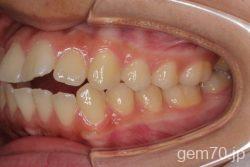

症状:開咬装置:セラミックブラケット | 抜歯世代:10代 | 高校生

主訴)前歯がかみ合わない

診断)開咬

年齢)18歳

使用装置)マルチブラケット装置

治療方法)抜歯 4|4/4|4

治療期間) 2年4ヵ月 通院回数 27回